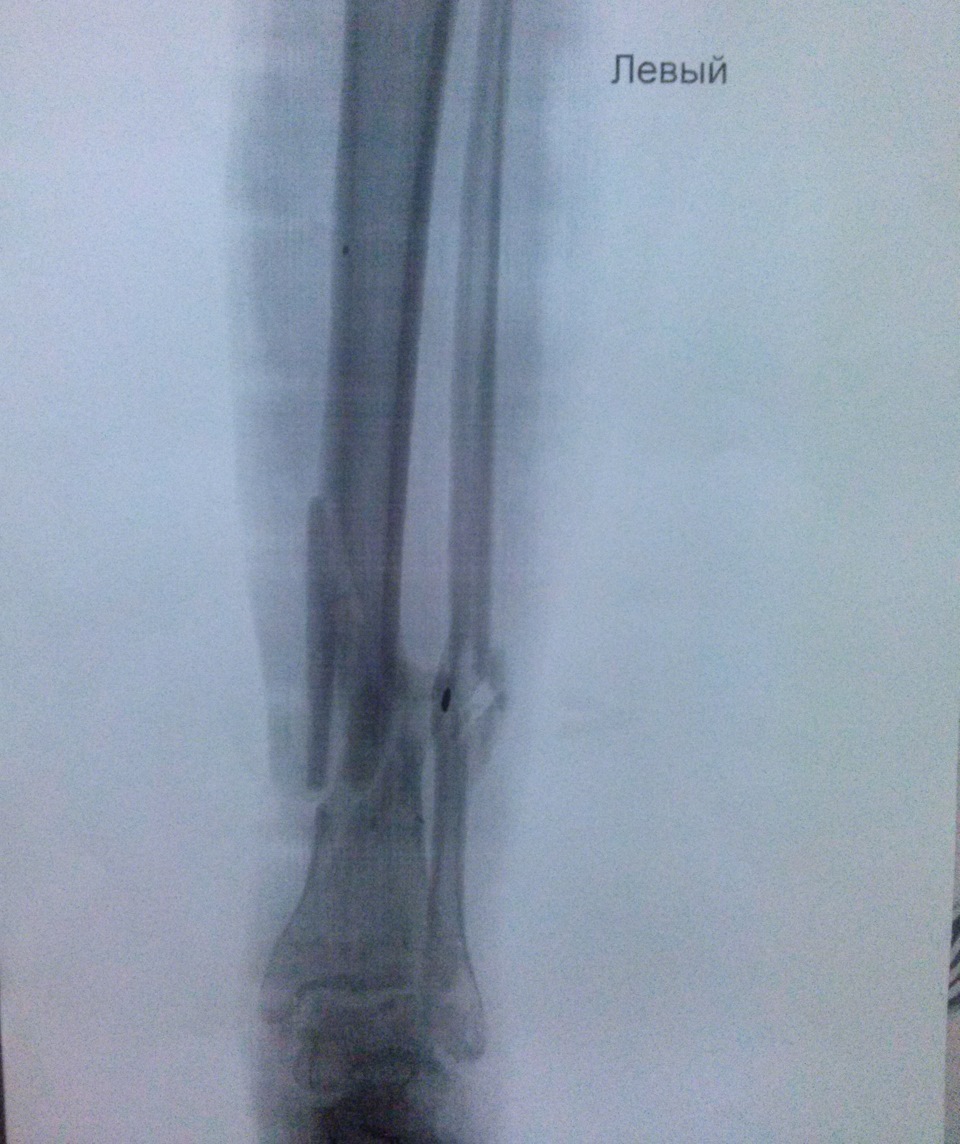

Рентгенограмма после демонтажа аппарата наружной фиксации

На рентген-контроле от 29 октября 2021 года, через 6,5 месяцев с момента первоначальной травмы, кости полностью срослись.

2 ноября 2021 года демонтировали аппарата Илизарова. Рана голени к этому времени зажила.

В ходе лечения левая нога стала короче на 4 см, но пациент свободно опирается на неё при ходьбе. Носит ортопедическую обувь.